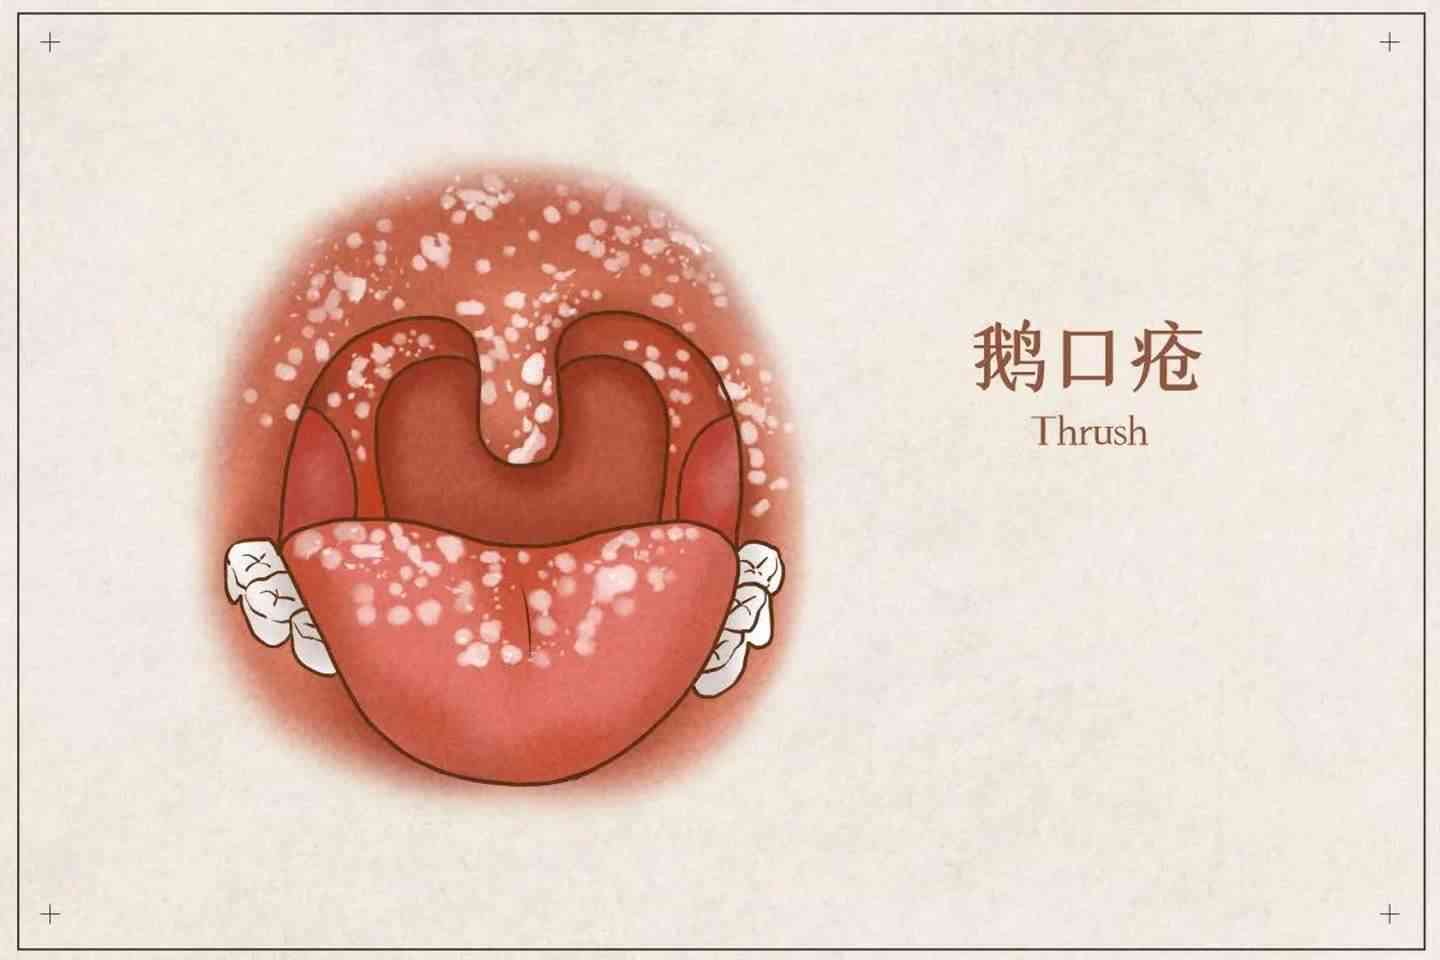

如何快速鉴别口疮和鹅口疮

图片尺寸529x421

小宝宝嘴里出现白点,小心真菌感染_鹅口疮

图片尺寸489x414